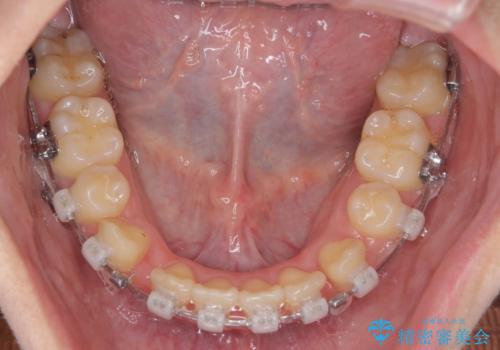

治療後は非常に歯ブラシがしやすくなったと、治療結果に満足いただくことができました。